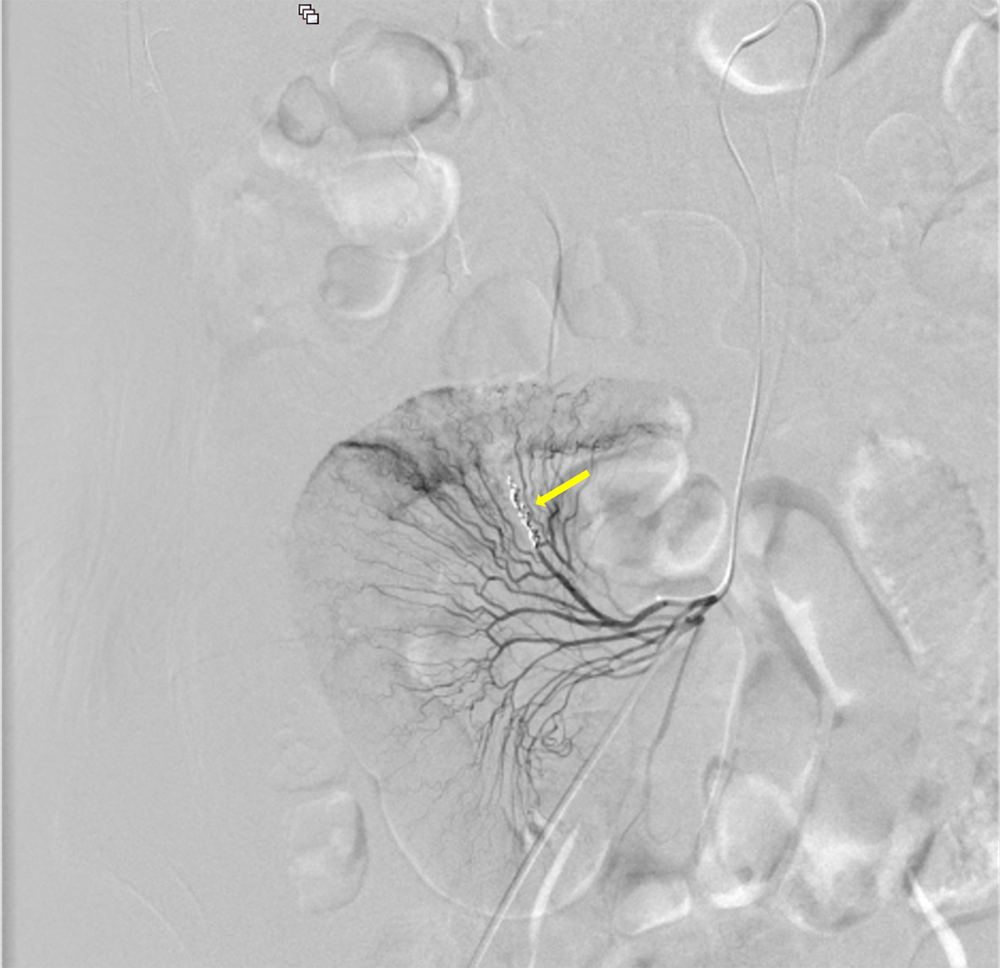

サイトメガロウイルス感染症を背景に下血がみられ消化管出血が疑われた。出血源の精査目的に造影CTが施行された。造影CTにて回腸で造影剤の血管外漏出像がみられ、出血源と考えられた。

造影CT撮像後、直ちに経カテーテル的血管塞栓術を施行し原因血管を金属コイルで塞栓し止血を得ることができた。